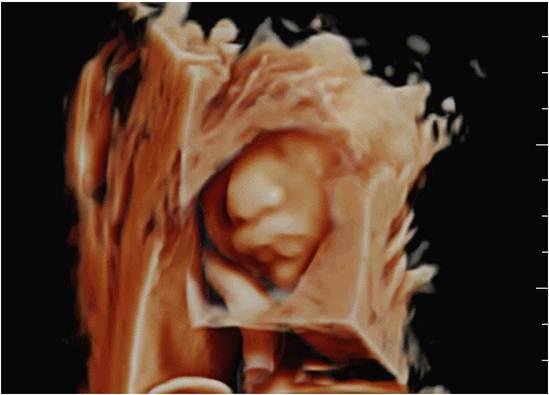

智能可视化-胎儿面部自动导航